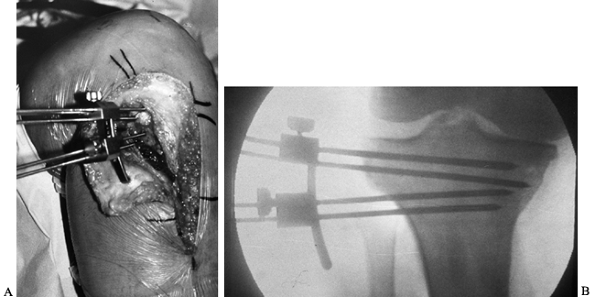

resection (Fig. 107.2). Exchange the variable-angle guide for proximal and distal cutting blocks (Fig. 107.3A), and perform cuts with an oscillating saw (Fig. 107.3B). The two arms of the osteotomy meet at a point just lateral to the medial cortex.

Figure 107.2. Tibial osteotomy angle cutting jig in place. B: Fluoroscopic view of angle cutting jig in place.